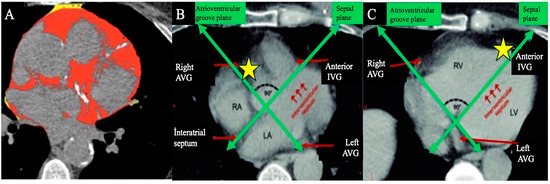

| Thorax CT—aortic calcification +, n (%) | 86 (%82.7) | 103 (%46.6) | <0.001 |

| Thorax CT CAC + aortic calcification + | 5.28 | 3.13–8.91 | <0.001 | 3.85 | 1.69–8.78 | 0.001 |

| C | CACS + Aort calcification + | 1 point |